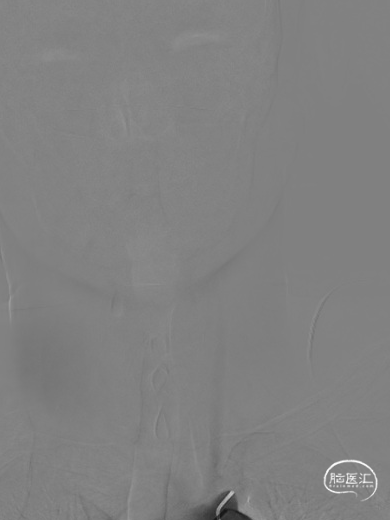

使用雅培 Command导丝顺利超选进入左椎V2段,冠脉3.0*12mm球囊进行扩张,在V18导丝的支撑下,在左侧椎动脉起始部植入一枚雅培4.5*15mm Herculink支架。支架植入后,造影提示椎动脉狭窄得到明显改善。

两侧桡动脉搏动基本对称,两侧肱动脉血压基本对称。